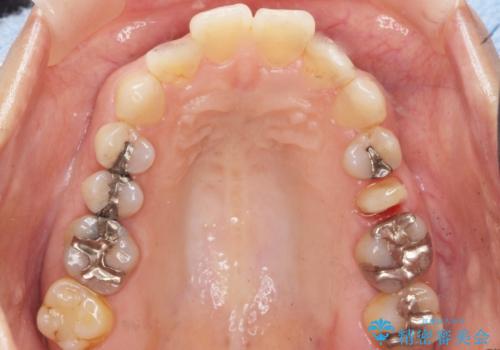

- 歯の根のあたりの歯ぐきを押すと痛むことを主訴に来院された患者様です。

精査したところ、左上の小臼歯(左上5)の神経が死んでいました。

根管治療後、セラミッククラウンによる補綴を行いました。